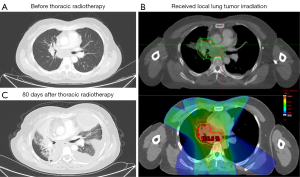

After developing TRP, most (58.9%) patients received systemic steroids, and 7 patients with co-infection received antibiotic therapy. Finally, 35 patients completely recovered or improved. However, a 45-year-old female patient with grade 5 TRP died of severe respiratory failure. This patient with stage IVB NSCLC progressed after receiving chemotherapy and oligoprogressed again after 4 months of alectinib treatment. Next, she received 45 Gy palliative TRT in 3 Gy daily fractions. The total lung V5, V20, V30 and MLD were 32.9%, 8.9%, 7.2% and 622.1 cGy, respectively. Eighty days after the end of TRT, the patient developed dyspnea and fever, and was diagnosed as TRP. As shown in Figure 2, the chest CT image depicts massive pleural effusion and diffuse infiltration lesions in the right lung. Three patients were lost to long-term follow-up.